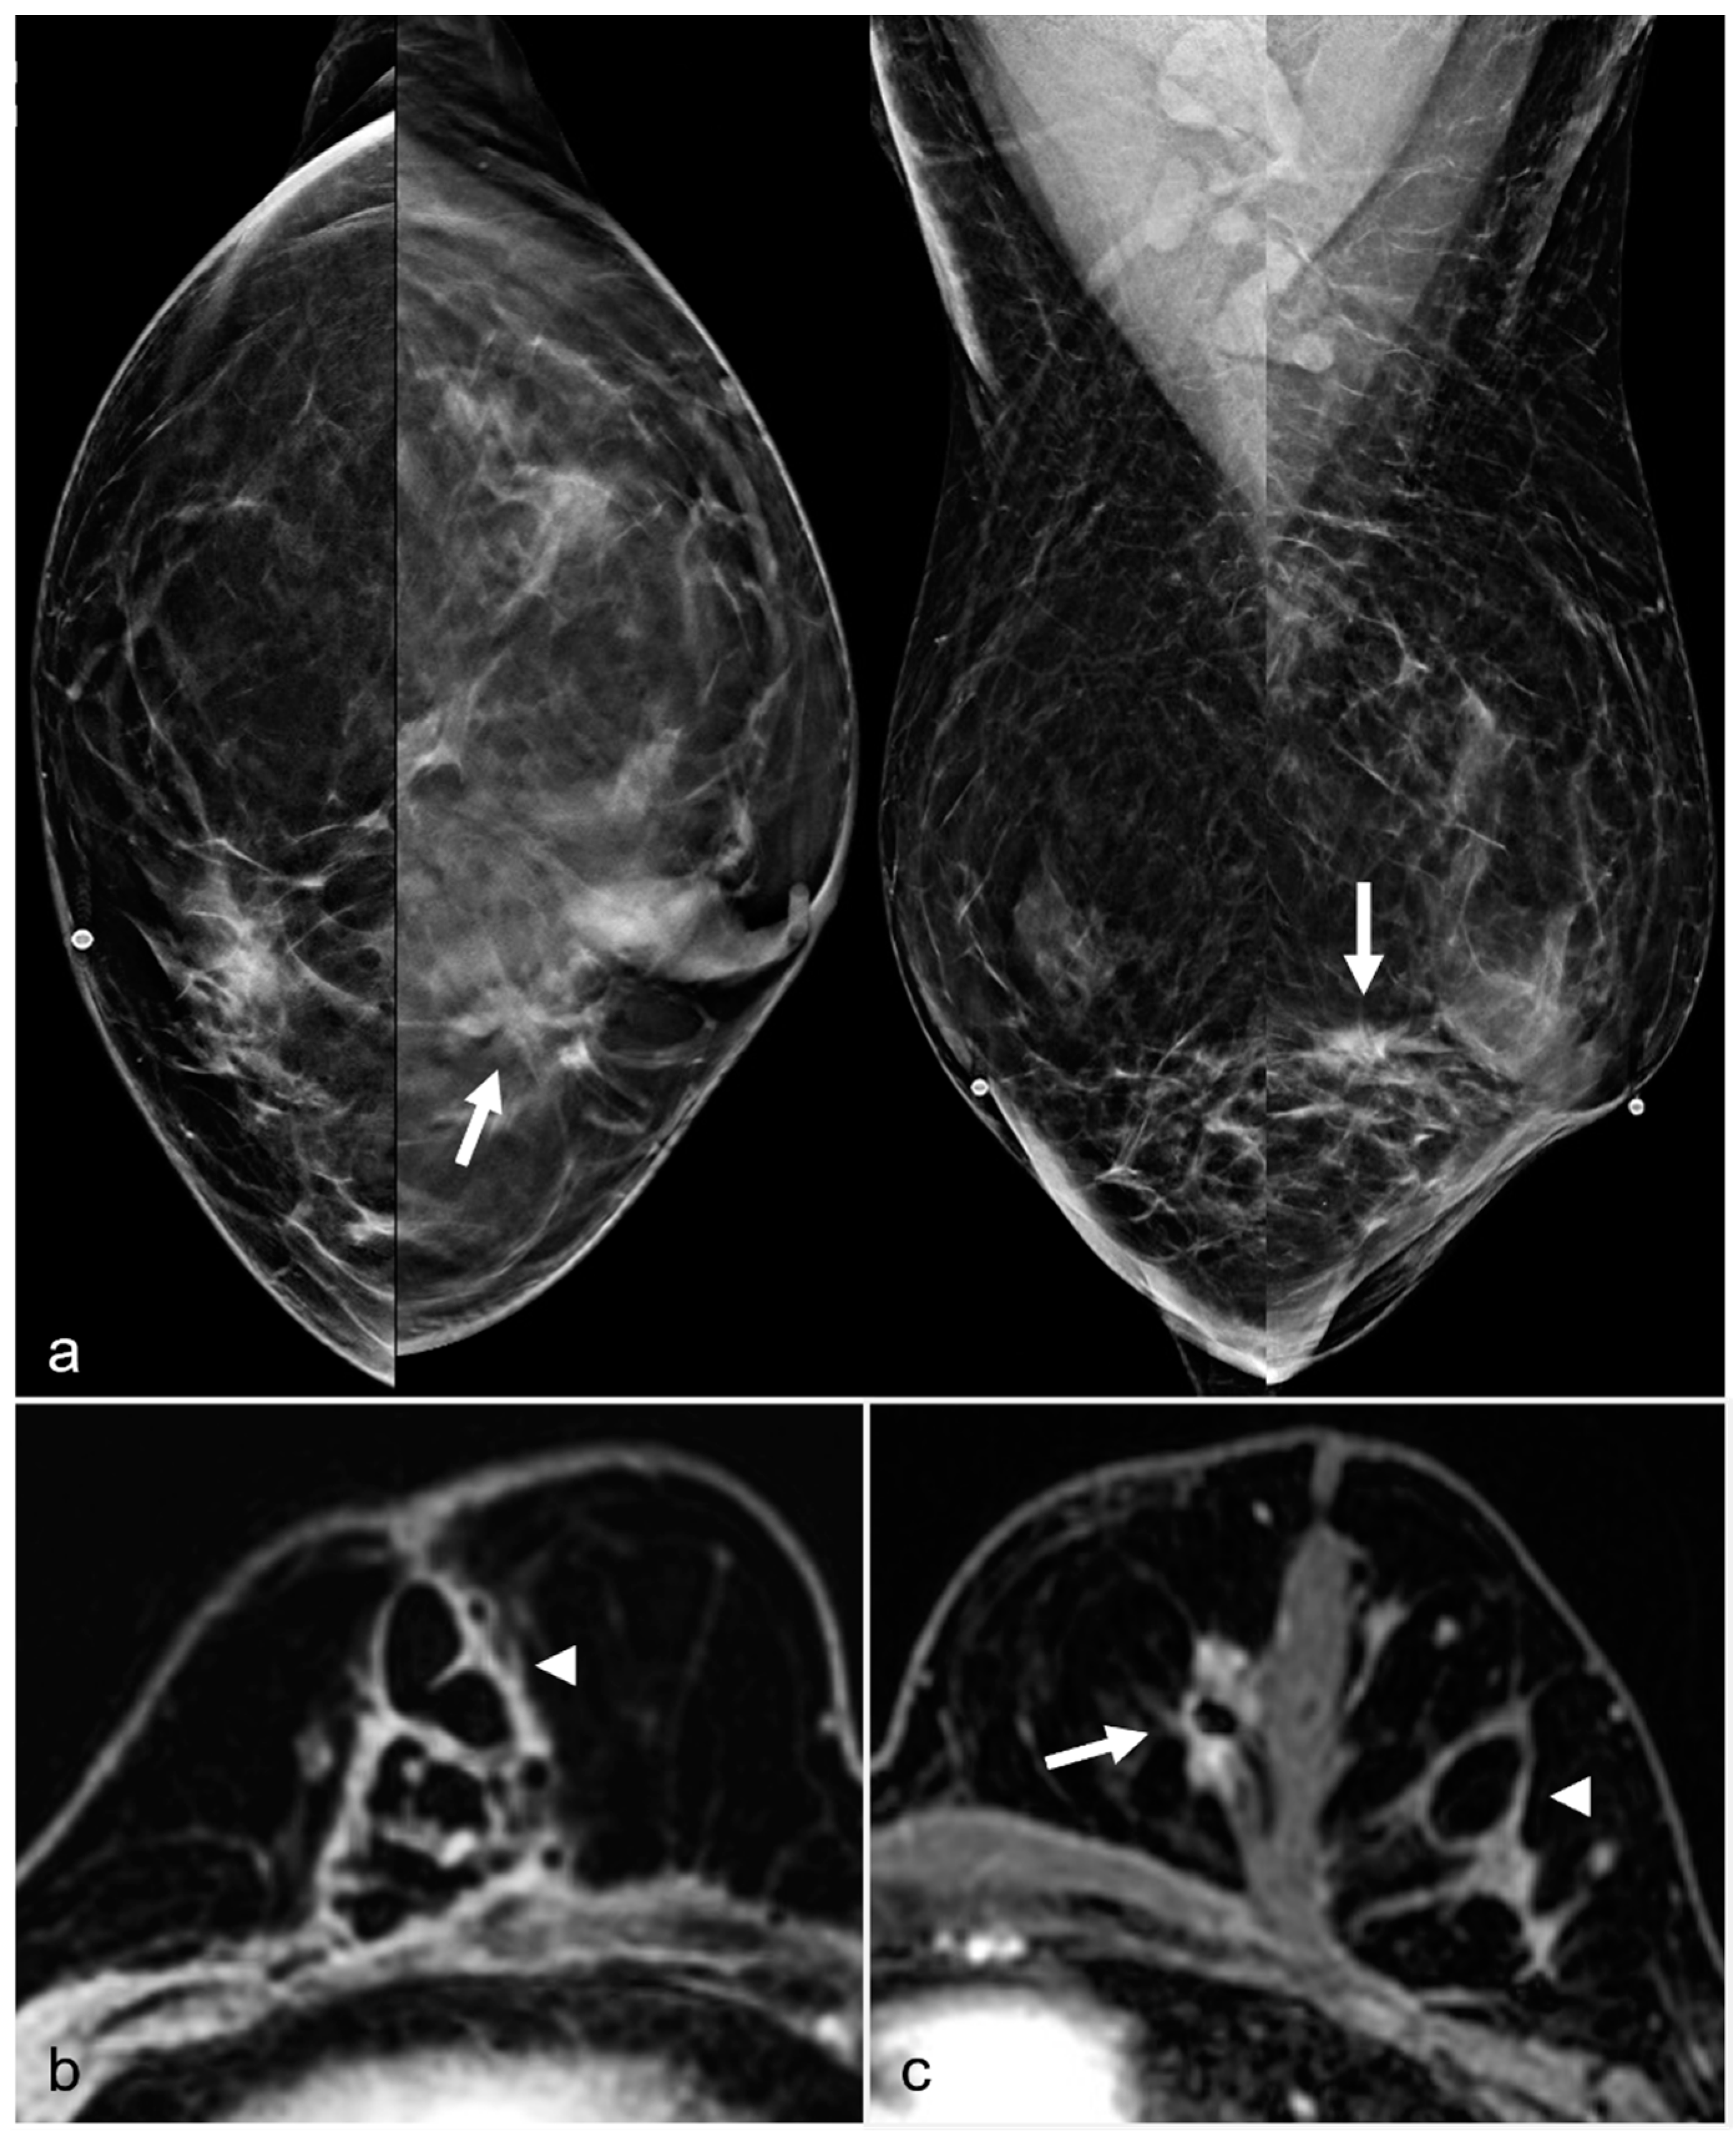

Figure 16. A 52-year-old woman with a history of subglandular silicone implants. Prior mammograms with implant displaced views were negative. A screening mammogram with bilateral CC and MLO views one year after BES (a) demonstrates a spiculated mass in the left lower inner quadrant (arrow), which was biopsied under ultrasound guidance with pathology revealing invasive ductal carcinoma. T1-weighted post-contrast MRI axial images demonstrate areas of fat necrosis in both breasts ((b,c), arrowheads). An enhancing mass with a biopsy clip is seen adjacent to the surgical scar ((c), arrow) in the left breast representing the biopsy proven carcinoma.